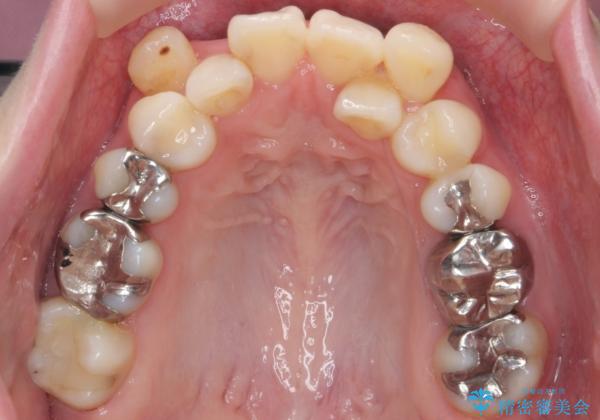

- 八重歯を主訴に来院。他院で全体ワイヤー矯正、4本抜歯で3-4年かかるかもしれないと説明を受けたとのこと。

八重歯の部分は抜歯し、奥に入っていた前歯を前に移動させました。

下の前歯は生まれつき3本だったため、さらに2本下を抜くとなると3本少なくなってしまうため、下の前歯を一本お取りして最小限の抜歯としました。

上にはワイヤー部分矯正を行った後、インビザラインでマウスピース矯正を行っています。

矯正治療後にしっかり全体の虫歯治療も行い、とても良い状態にできたと思います。

犬歯を抜いたとしても、矯正治療を短期間で終わらせて歯に負担がかからないようにし、虫歯治療その分しっかり行うのもメリットがあるのではないかと思います。

今回は特に左上の犬歯は歯肉退縮して根が露出していたのもあり、抜歯をお勧めしました。